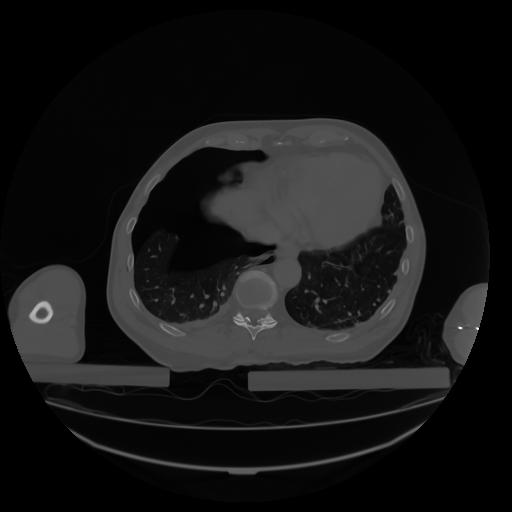

27 CUERPO,CE,Axial,3.0,CUERPO,,